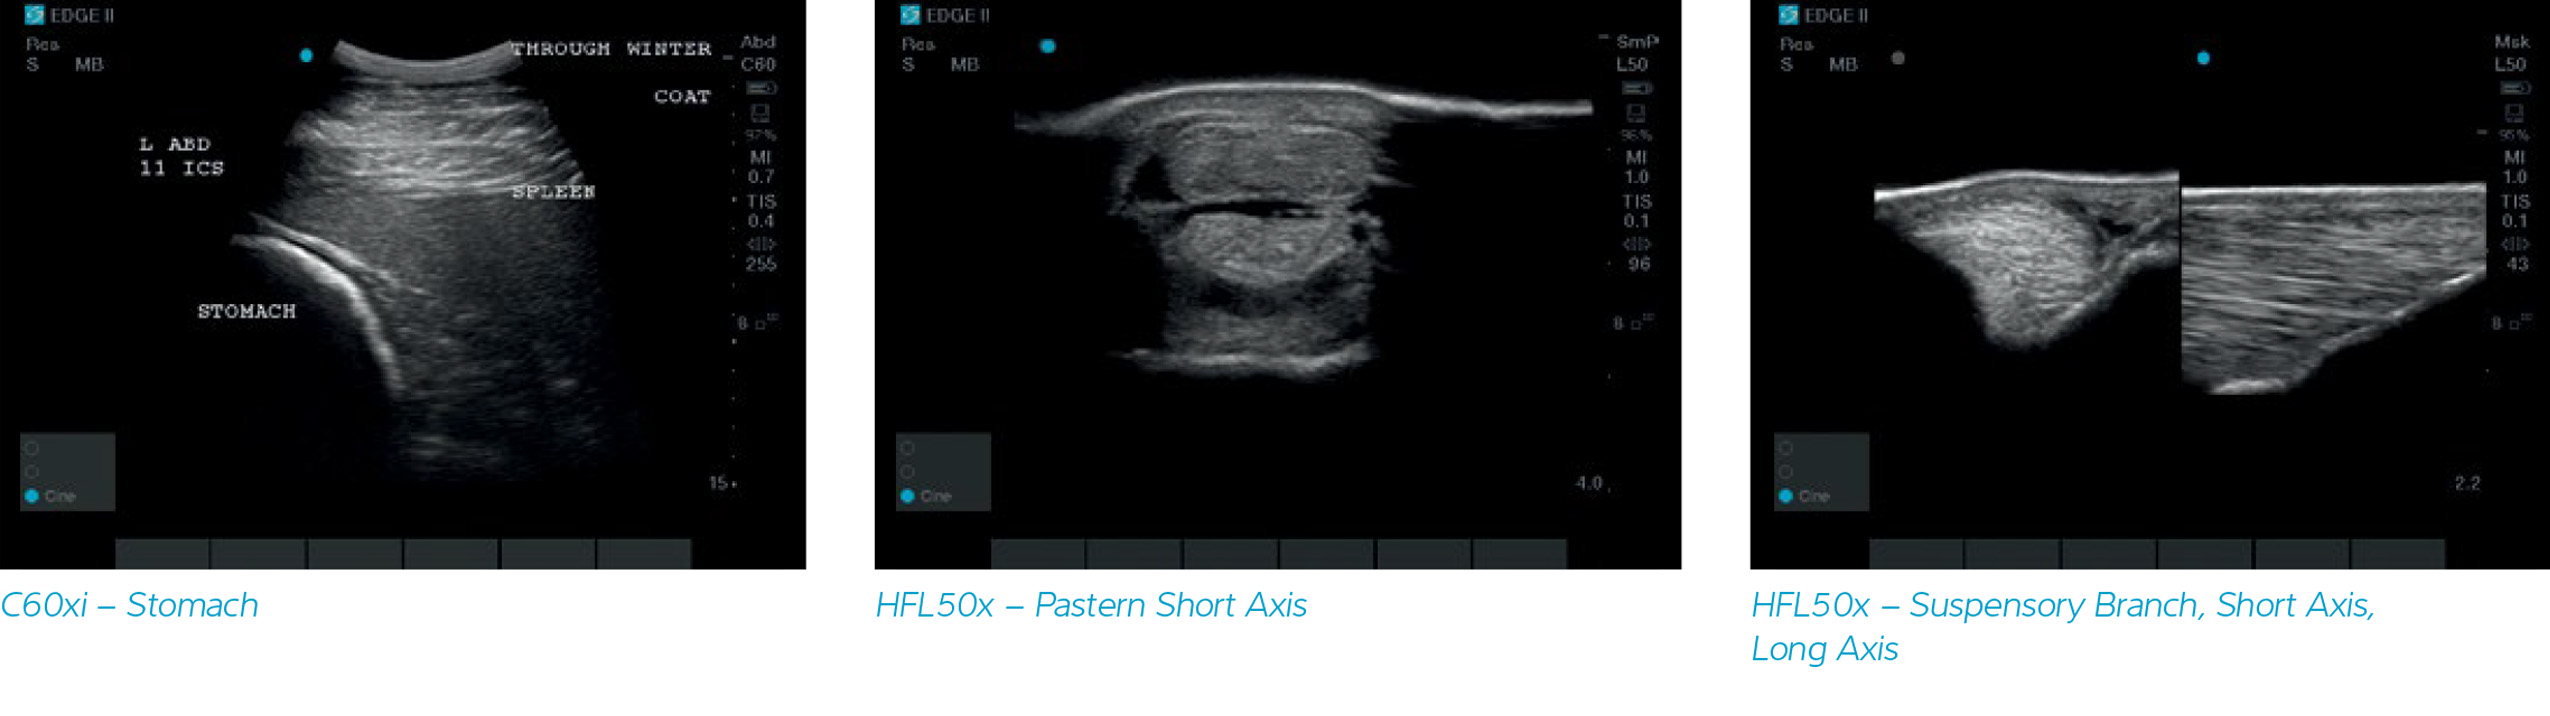

Now, with a new sealed keyboard and shielded cable transducers, the Sonosite Edge II Vet ultrasound was developed to withstand your most challenging workday.

DirectClear Technology combines several new design features for significant performance improvement. Compared to the previous generation of transducers, tests have shown an increase of up to 30% in penetration and resolution with these new additions. DirectClear Technology is available on several transducers across the SonoSite ultrasound portfolio